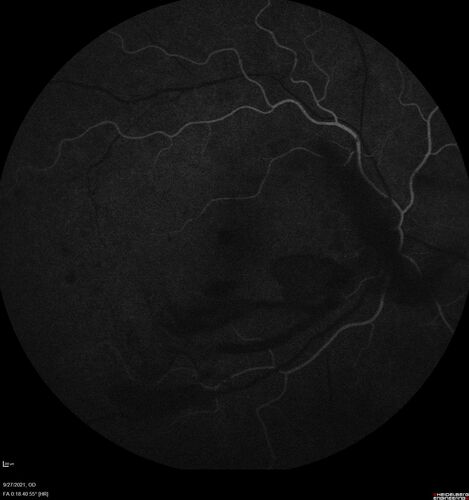

Severe Proliferative Diabetic Retinopathy and Good Vision

49 year old man with vision loss in the right eye for 2 weeks. VA 20/40 OD, 20/63 OS. DM x 15 years and HTN.